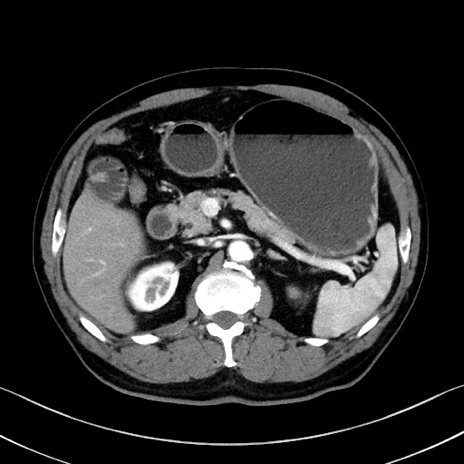

症例35(横断像)

【症例】70歳代 男性

【主訴】腹部膨満、嘔吐

【現病歴】昨日より腹部膨満感出現。本日増悪し、仙痛出現。嘔吐あり、受診。

【既往歴】糖尿病、胆摘後

【身体所見】BP 149/80mmHg、HR 74/min、BT 35.9℃、腹部:膨満、軟、圧痛なし。腸雑音減弱あり。上腹部正中切開瘢痕あり。

【データ】WBC 13500、CRP 1.72